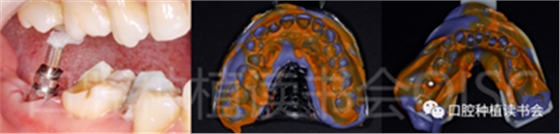

5.1 術(shù)前情況:

患者為70歲女性,右下后牙樁核冠因遠(yuǎn)中牙根縱裂脫落,全身健康狀況良好,輕度骨質(zhì)疏松??趦?nèi)檢查:47殘根,遠(yuǎn)中根縱裂,部分根面已腐至齦下2mm,叩(++),松(-);48近中傾斜阻生,咬合關(guān)系、修復(fù)間隙及牙周情況正常(圖12)。

圖12 遠(yuǎn)中根縱裂及根面齲導(dǎo)致47殘根無(wú)法保留。

術(shù)前CBCT(美亞光電)檢查:47根分叉下方骨高度及骨寬度滿足即刻種植要求(圖13)。

圖13 47根分叉區(qū)骨寬度及骨高度(與下頜神經(jīng)管之間的距離)滿足即刻種植要求。